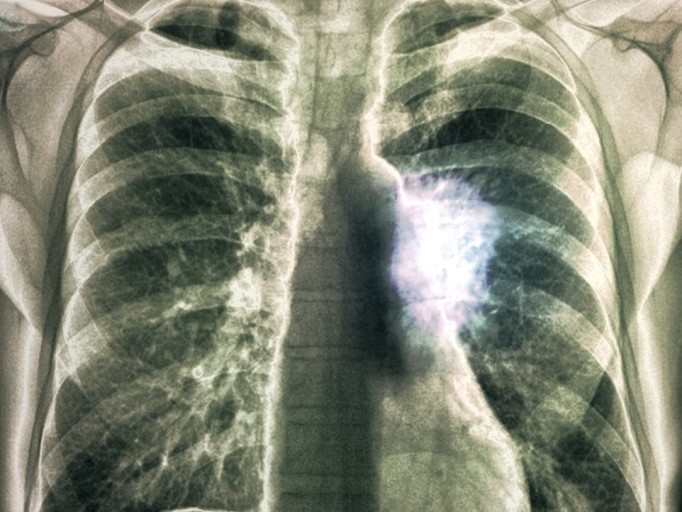

9. 흉부 고통

폐암에 걸리면 흉부에 고통이 느껴져요. 폐의 가장자리에 생긴 폐암이 흉막과 흉벽을 침범해서 고통이 생기는 것으로 가슴이 답답하면서 꽉 막힌 느낌이 지속되며 날카롭게 찌르는 듯한 느낌과 압력 하는 느낌 등 여러 가지 고통이 나타납니다.